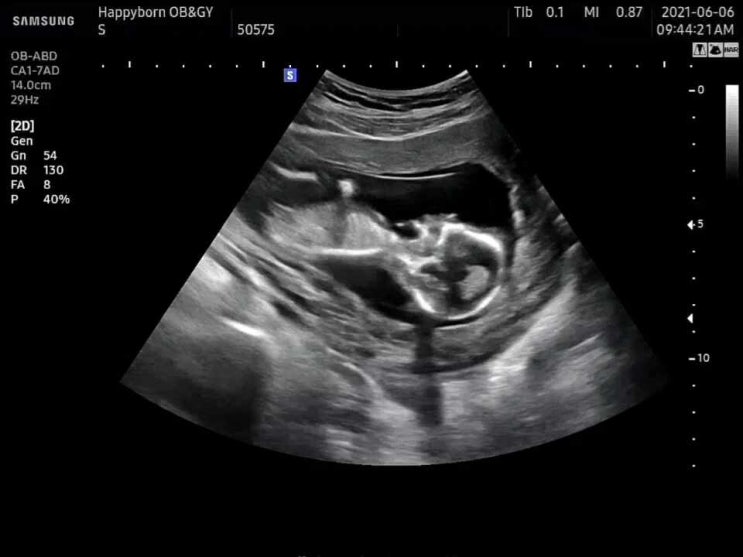

임신27주차/ 입체초음파

#입체초음파 #27주차 #27주아기무게 아주아주 오랜만에 블로그를 쓴다. 쉬는날도 많았는데 쓸데 없이 바빴...